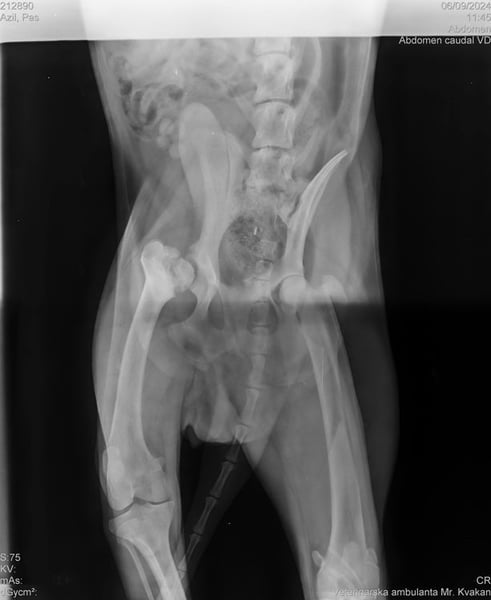

Wir durften ihn deshalb ohne Probleme mit ins Tierheim nehmen, da Yondu Probleme mit der Hüfte und ein etwas kürzeres Beinchen hat. Youdu hat bei einen Besuch beim Tierarzt entsprechende Röntgenbilder von Hüfte und Hinterbeinchen, die den Interessierten in der Bildergalerie zur Verfügung gestellt werden.